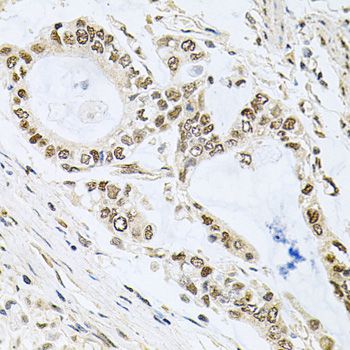

BCL2, Polyclonal Antibody (Cat# AAA28239)

BCL2, Polyclonal Antibody (Cat# AAA29670)